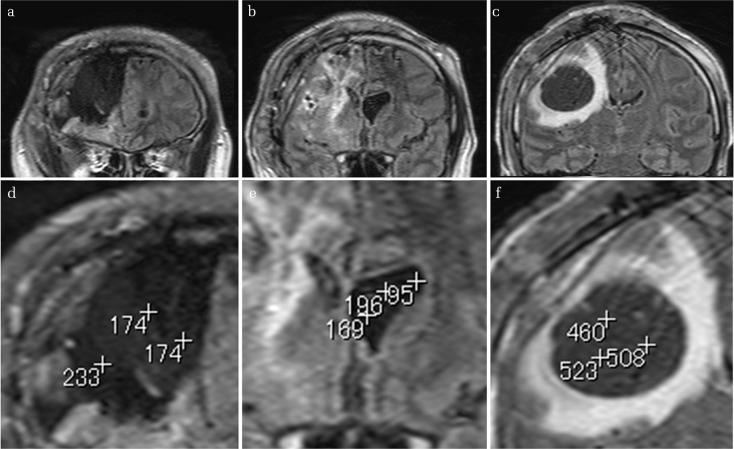

A 43-year-old man was operated on for right frontal oligoastrocytoma. 14 years after the surgery, magnetic resonance imaging and positron emission tomography revealed a new lesion near the surgical cavity. He underwent gross total resection of the lesion and implantation of bis-chloroethylnitrosourea (BCNU) wafers after intraoperative pathological diagnosis of recurrent high-grade glioma. A few days after the operation, the level of consciousness gradually worsened and left hemiparesis developed. A computed tomography scan revealed a cyst remote to the surgical cavity which did not exist 3 days prior. We performed anterior cyst wall fenestration and removed all wafers. The characteristic pathological finding at the wafer implantation site was severe inflammation within and around small vessels. This inflammatory reaction was not seen on the surface of the brain parenchyma. After surgery and rehabilitation, the patient's Karnofsky Performance Status stabilized to a pre-incident score of 90 and he returned to work. The exact pathophysiological mechanism of the cyst was not clear, but check-valve and/or osmotic gradient mechanisms related to BCNU wafer implantation could have contributed to this phenomenon. As remote cyst development happened a week after surgery, surgeons should be aware of such a rare condition when implanting wafers as consciousness impairment and hemiparesis may occur. Close radiological follow-up is therefore necessary.

一名43岁男性因右侧额叶少突星形细胞瘤接受手术。术后14年,磁共振成像和正电子发射断层扫描显示手术腔附近出现新病灶。术中病理诊断为复发性高级别胶质瘤后,他接受了病灶的大体全切并植入了双氯乙基亚硝脲(BCNU)晶片。术后几天,意识水平逐渐恶化并出现左侧偏瘫。计算机断层扫描显示手术腔远处有一个囊肿,而3天前并不存在。我们进行了前囊肿壁开窗术并取出了所有晶片。晶片植入部位的特征性病理发现是小血管内部及周围有严重炎症。脑实质表面未见这种炎症反应。经过手术和康复治疗,患者的卡氏功能状态评分稳定在发病前的90分,他恢复了工作。囊肿的确切病理生理机制尚不清楚,但与BCNU晶片植入相关的单向阀和/或渗透梯度机制可能导致了这种现象。由于术后一周出现了远处囊肿,外科医生在植入晶片时应意识到这种罕见情况,因为可能会出现意识障碍和偏瘫。因此,密切的影像学随访是必要的。